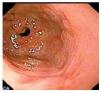

Se le realizó gastroscopia y colonoscopia que mostraron gastritis erosiva antral y duodenitis leve, así como enfermedad diverticular de colon no complicada, un pólipo en colon transverso y tres pólipos a nivel de colon sigmoides, realizándose polipectomía con recuperación de las lesiones para análisis histopatológico (Figura 2). Se tomaron biopsias complementarias del duodeno y diversos segmentos del colon que mostraron la presencia de macrófagos subepiteliales positivos a la tinción de ácido peryodico de Schiff (PAS) y negativa a la tinción de Ziehl-Nielsen, compatible con enfermedad de Whipple (Figura 3). Se modificó el tratamiento iniciando ceftriaxona por vía intravenosa durante dos semanas con desaparición de la diarrea a las 24 horas de haber iniciado el manejo. Egresó con doxiciclina y se mantuvo en vigilancia durante seis meses, durante los cuales estuvo asintomática.

¿ Figura 3. Biopsia de colon transverso; se observan macrófagos subepiteliales vacuolados positivos a la tinción de PAS, 100x.